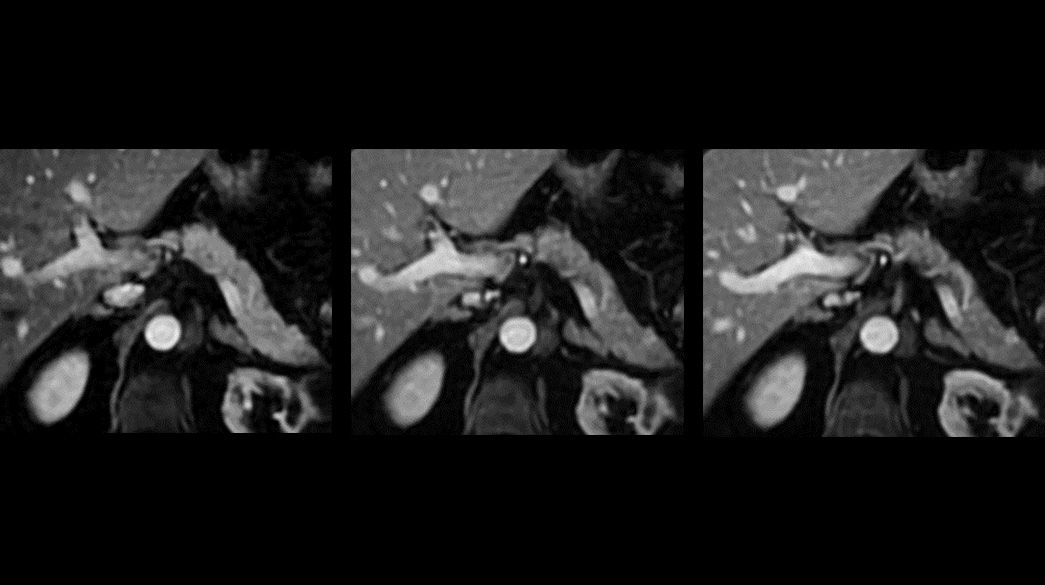

BreView1040-x-585

Radiation Oncology

MRI-Planner1040-x-585

AIR-RT-Coils-suite1040-x-585